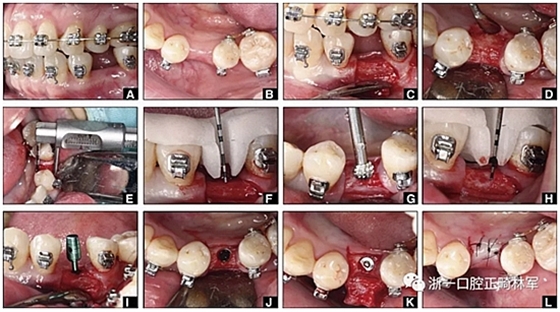

經(jīng)過(guò)32個(gè)月的活動(dòng)治療后,上下牙弓排齊良好,下頜第一磨牙區(qū)的雙側(cè)牙間隙可用于種植(圖12,A和13,A)。

圖12.將種植體植入正畸產(chǎn)生的間隙中的步驟:A,將下頜左側(cè)第二前磨牙向遠(yuǎn)中移動(dòng)以在前磨牙之間產(chǎn)生間隙; B,種植部位的咬合面觀; C,一個(gè)水平切口和兩個(gè)垂直切口,距相鄰牙齒1.5mm的距離; D,暴露的牙槽嵴的咬合面觀; E,測(cè)量牙槽嵴的寬度約6mm; F,手術(shù)導(dǎo)板顯示預(yù)備冠頸部的位置距離骨牙槽嵴頂僅1毫米; G,用球鉆修整牙槽嵴; H,建立3mm從手術(shù)導(dǎo)板的頸部輪廓到骨嵴的距離,以實(shí)現(xiàn)必要的生物學(xué)寬度; I,引導(dǎo)針顯示了截骨的角度; J,3.5×10mm種植體完全置于骨內(nèi); K,一個(gè)覆蓋螺帽就位; 和L,縫合。

圖13. A,下頜右側(cè)第一磨牙區(qū)缺牙區(qū)咬合面觀; B,做1個(gè)水平的冠狀切口和2個(gè)垂直切口; C,暴露牙槽嵴; D,放置導(dǎo)針確保合適的就位道; E,放置3.5×10mm種植體; F,有暴露的種植體界面(粗糙表面); G,連接愈合基臺(tái),并將骨粉(凍干的同種異體骨和Bio-Oss)置于頰側(cè)以覆蓋暴露的種植體表面; H,縫合。